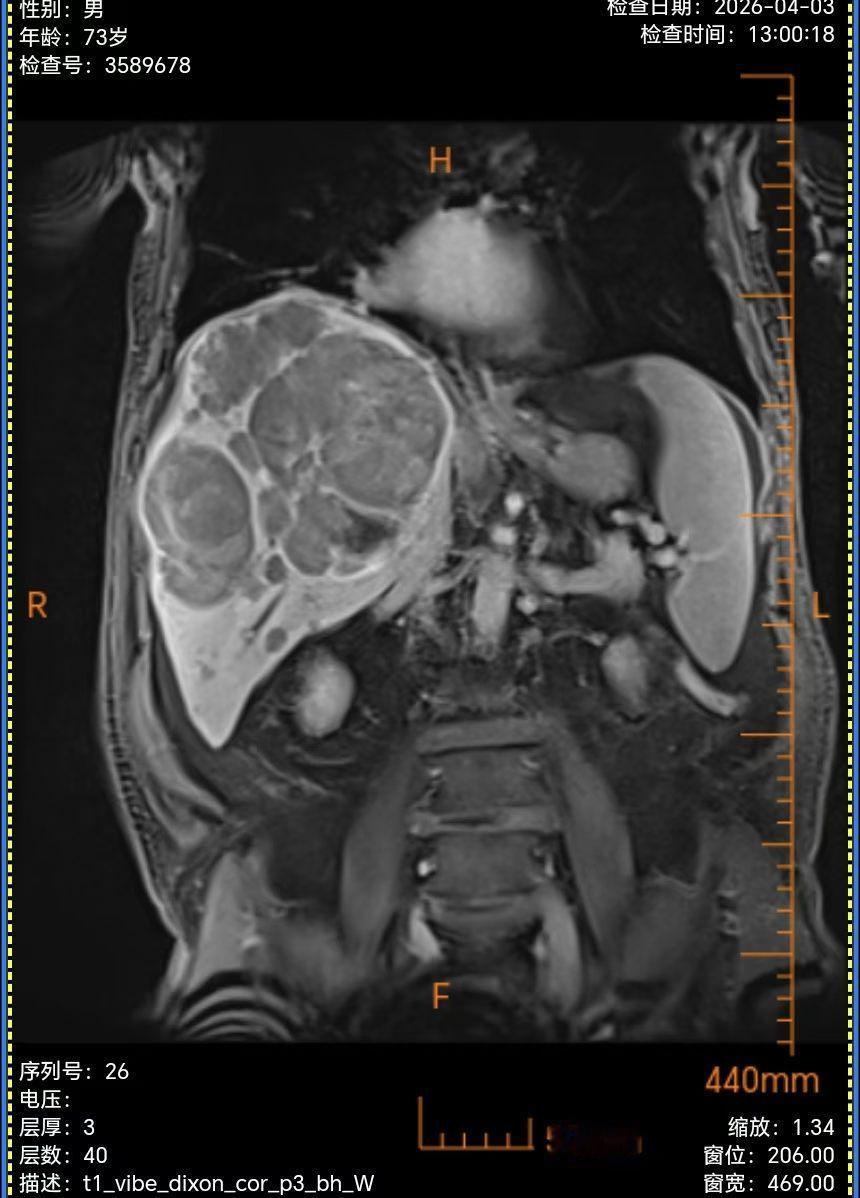

不放弃才会有奇迹肝癌 海扶刀